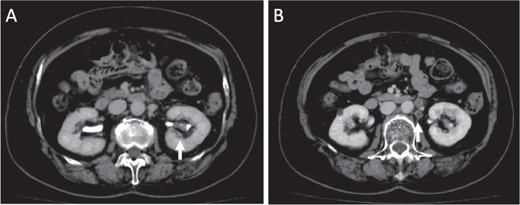

Microscopical photographs of the tumor. Microscopical photographs of the tumor stained by hematoxylin and eosin staining. Original magnifications of the objective lens of A, B, C and D are ×4, ×20, ×20 and ×20, respectively.

Initially, chemotherapy using gemcitabine (1300 mg/body) plus cisplatin (94 mg/day) was started 1 month after her initial visit, resulting in progressive disease. Subsequently, methotrexate, vinblastine, adriamycin and cisplatin therapies (methotrexate, 30–39 mg/body/day; vinblastine, 3.0–3.9 mg/body/day; Adriamycin, 30–39 mg/body/kg; cisplatin, 70–92 mg/body/day) were started. A total of four courses of the therapy were performed, with no effect on the tumor size. Therefore, nephrectomy of her left kidney and dissection of the regional lymph nodes were performed 8 months after her initial visit to the hospital. As shown in Fig. 2, the tumor was observed in the lower part of the pelvis to the parenchyma of the left kidney during macroscopic examination. The tumor size was 35 × 25 × 20 mm, and the color of the tumor was whitish yellow (Fig. 2). Histologically, the tumor consisted of elongated tubular structure and spindle cells with mucinous stroma (Fig. 3A and B). The spindle cell showed enlarged nuclei and prominent nucleoli, suggesting Fuhrman grade 4 (Fig. 3C). Partially, macrophages were prominent in the tumor (Fig. 3D). Alcina blue-positive mucin was also observed in the stroma of the tumor (Fig. 4A). Although the tumor projected to the renal pelvis, the tumor was lined with normal urothelial cells.